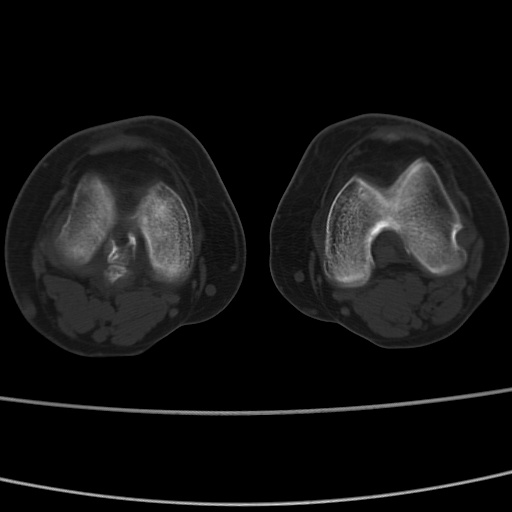

女性,50岁。【请提供患者临床症状体征】

右膝关节退行性改变,关节游离鼠。

右膝关节退行性改变,滑膜黏液囊钙/骨化并游离。

右膝关节退行性改变